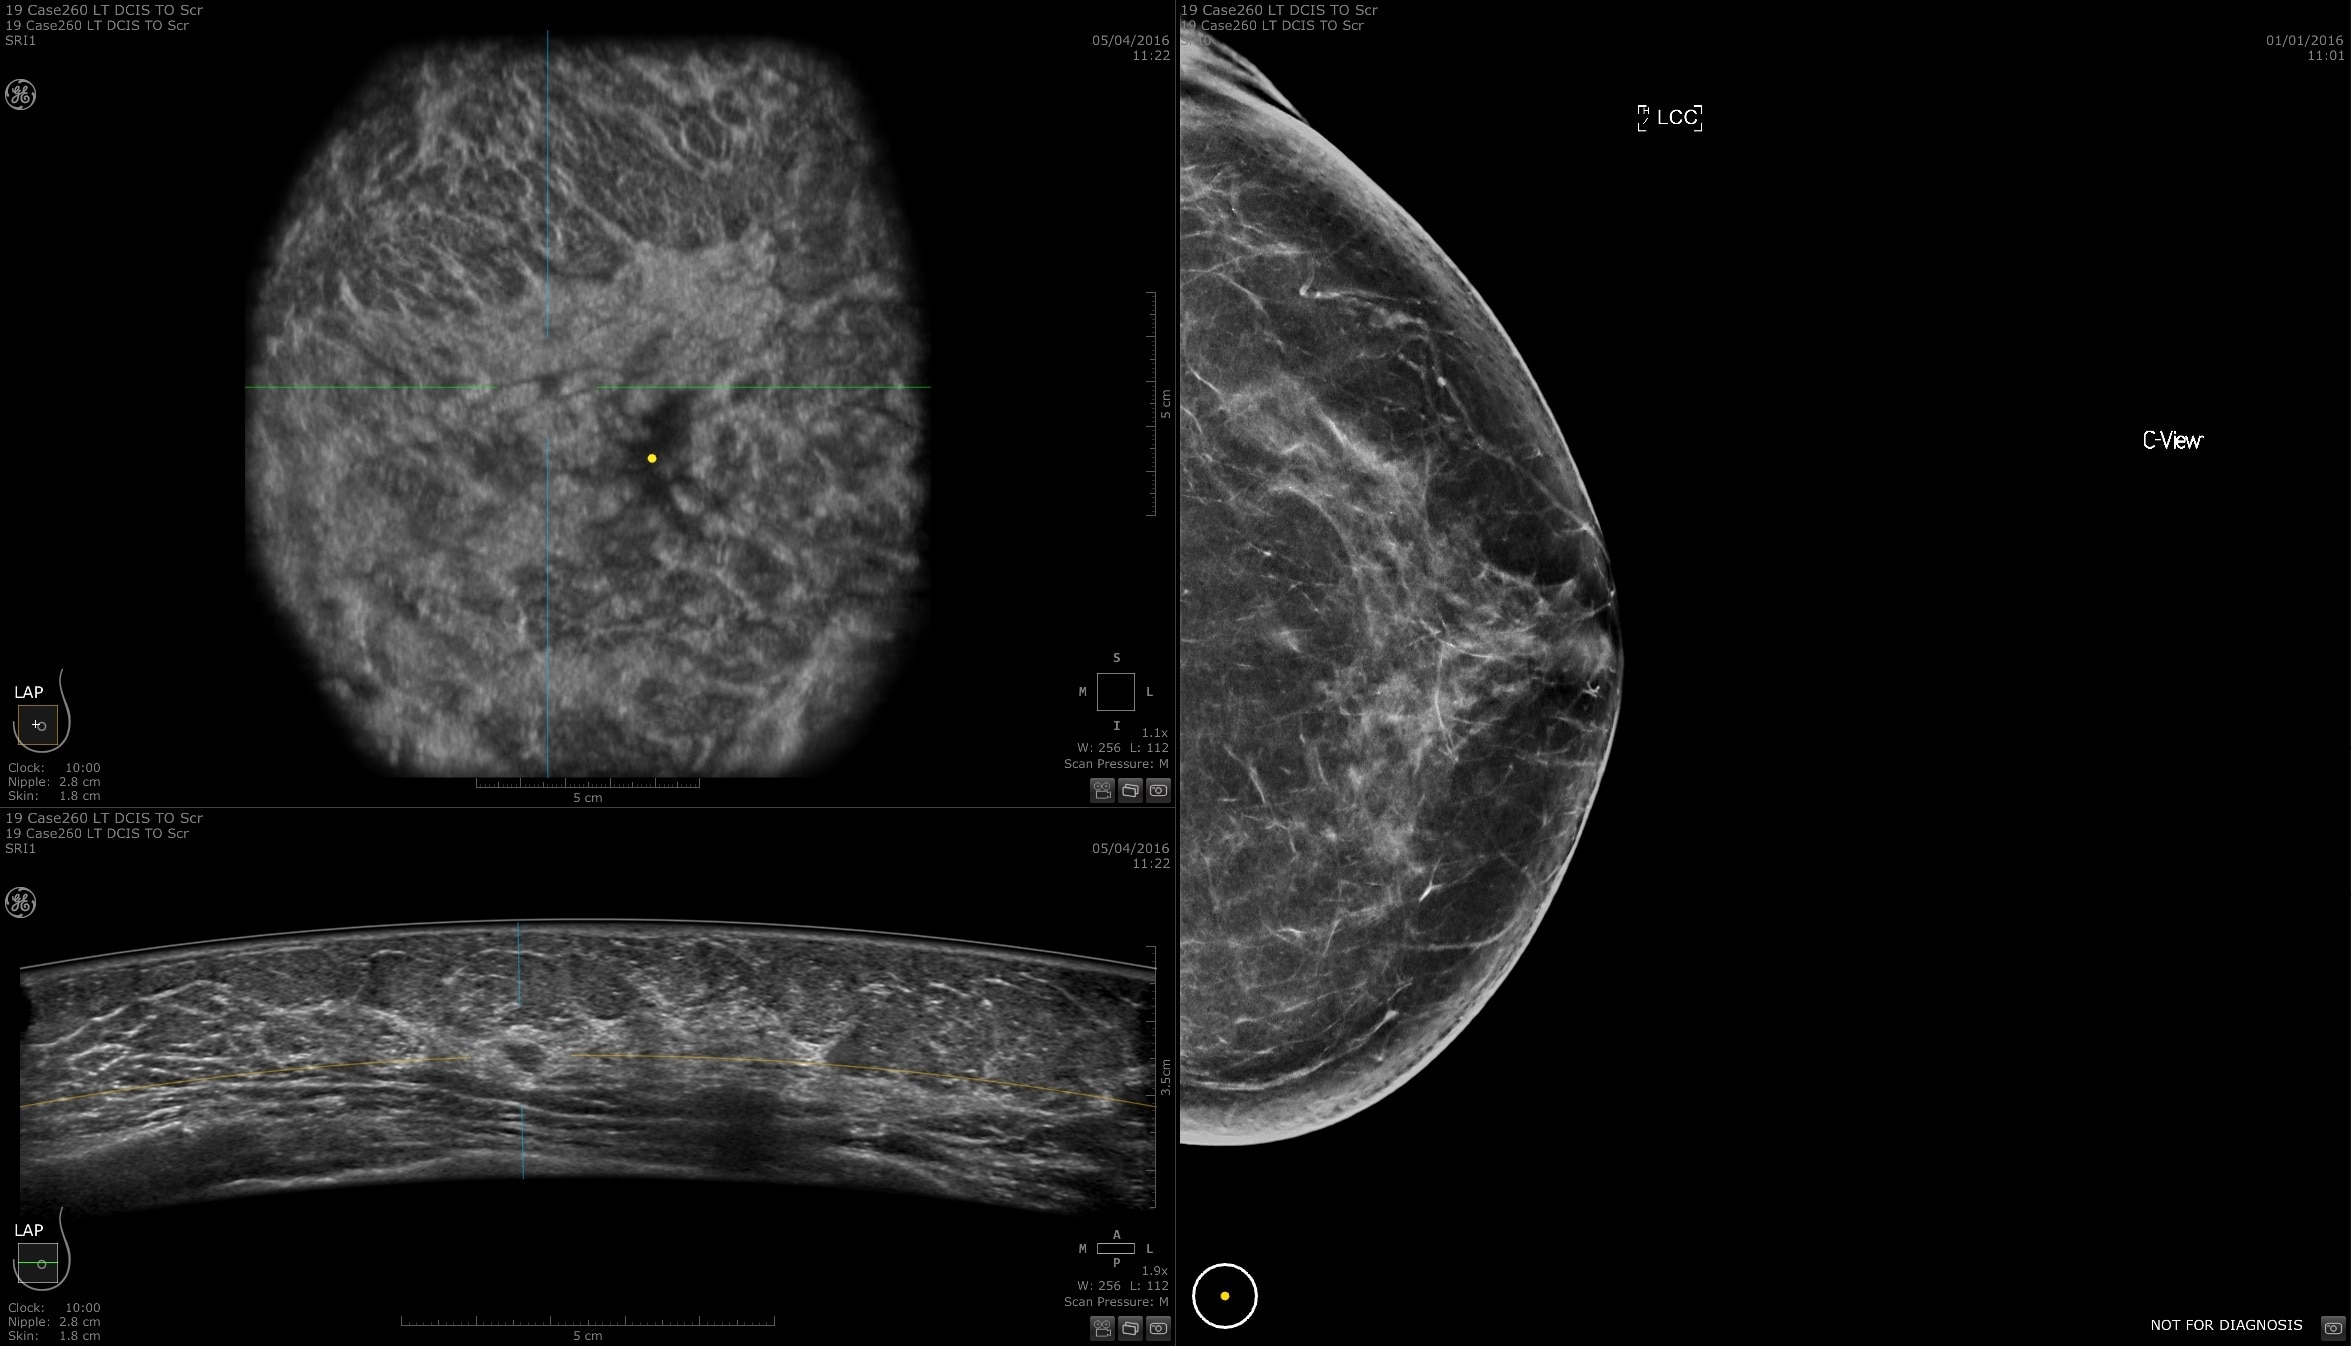

Dense breast tissue and cancer appear white on a mammogram, potentially camouflaging small cancers. Invenia ABUS 2.0, is specifically designed to help clinicians find cancers that may be hidden on mammography1,2.

SCREENING

The power of early cancer detection

Supplemental screening with Invenia ABUS 2.0 transforms breast care from reactive to proactive. When used in addition to mammography, Invenia ABUS 2.0 can improve breast cancer detection by 55 percent over mammography alone5. Women whose breast cancer is detected at an early stage have a 90% or higher survival rate6.